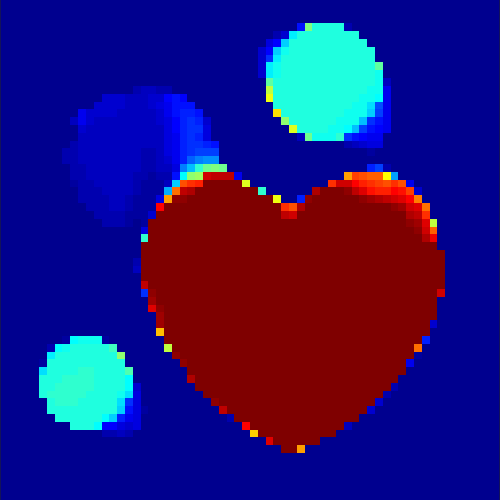

The first data set consists of a heart-shaped region and three circles on a static background (see figure 1 (a)). The two smaller circles are assumed to belong to

the same tissue type and therefore to the same subregion, which causes a total of four subregions, including the background. To simulate a more realistic application of dynamic SPECT

imaging, we used a synthesized representation of a rat liver as a second data set (see figure 1 (b)). The temporal concentration curves used to simulate the data sets

are shown in figure 2. As before, the total number of subregions was chosen to be equal to four in order to provide a both simple and realistic shape model.

As one can see in both figures, the reconstruction method applied to each data set performs very well, especially in contrast to the simple alternating EM method. This clearly shows the benefits of the proposed regularization methods. In case of noise-free given data, the shape of every object, where especially the heart is of higher interest, is clearly defined. As expected, we often observe errors in the edges of each region and where two regions are directly connected (the heart and the upper left circle). This causes the algorithm to incorrectly assign these pixels to another region. Furthermore, the reconstruction difficulties increase with an increase in noise. Some more pixels are assigned to the wrong region, which leads to a small hole-like structure within the heart region and causes a slight blurring effect. In the second data set the method clearly outperforms several other approaches by providing very clearly defined regions and even reconstructing fine structures of the phantom. However, as mentioned before, a clear reconstruction of the rat liver required highly optimized parameter sets, which makes the whole problem quite susceptible to parameter changes.